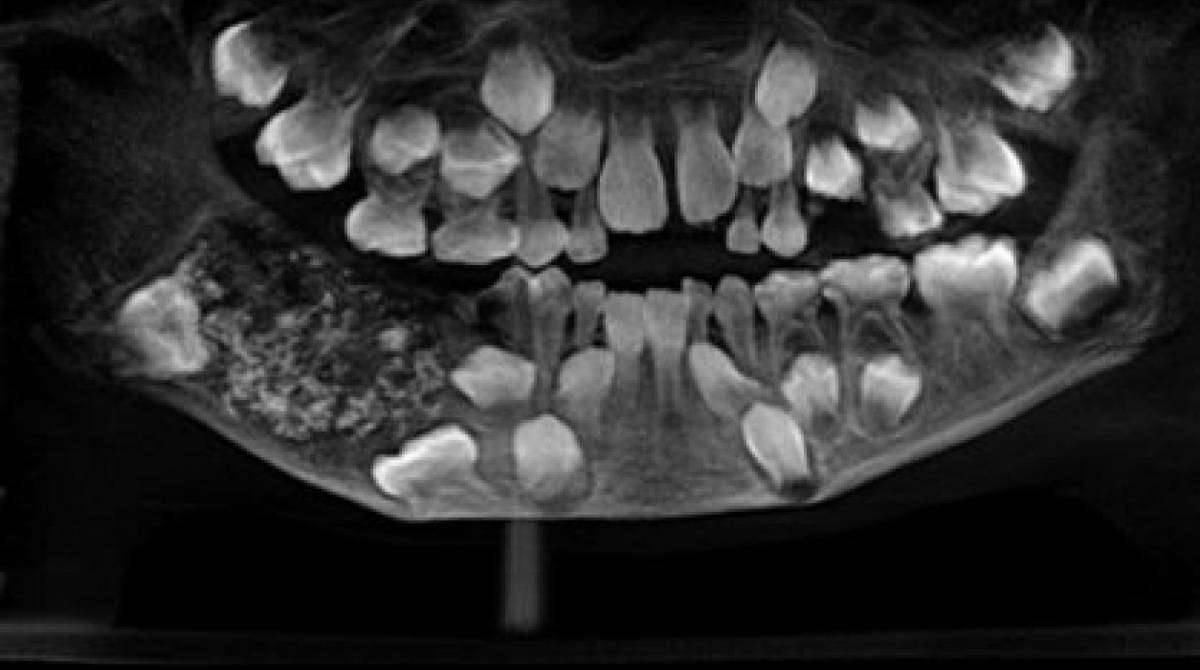

Segundo a doutora Prathiba Ramani, em entrevista à CNN, o raio-x do menino mostrou que a parte inferior do maxilar apresentar uma alta quantidade de “dentes anormais”. A cirurgia, no mês passado, retirou esses dentes que foram examinados pelos médicos.

Foram cinco horas para remover todos os dentes. “Era um total de 526 dentes, de 1 milímetro até 1,5 centímetro. Até as menores parte possuíam coroa e raízes”, afirmou Ramani.